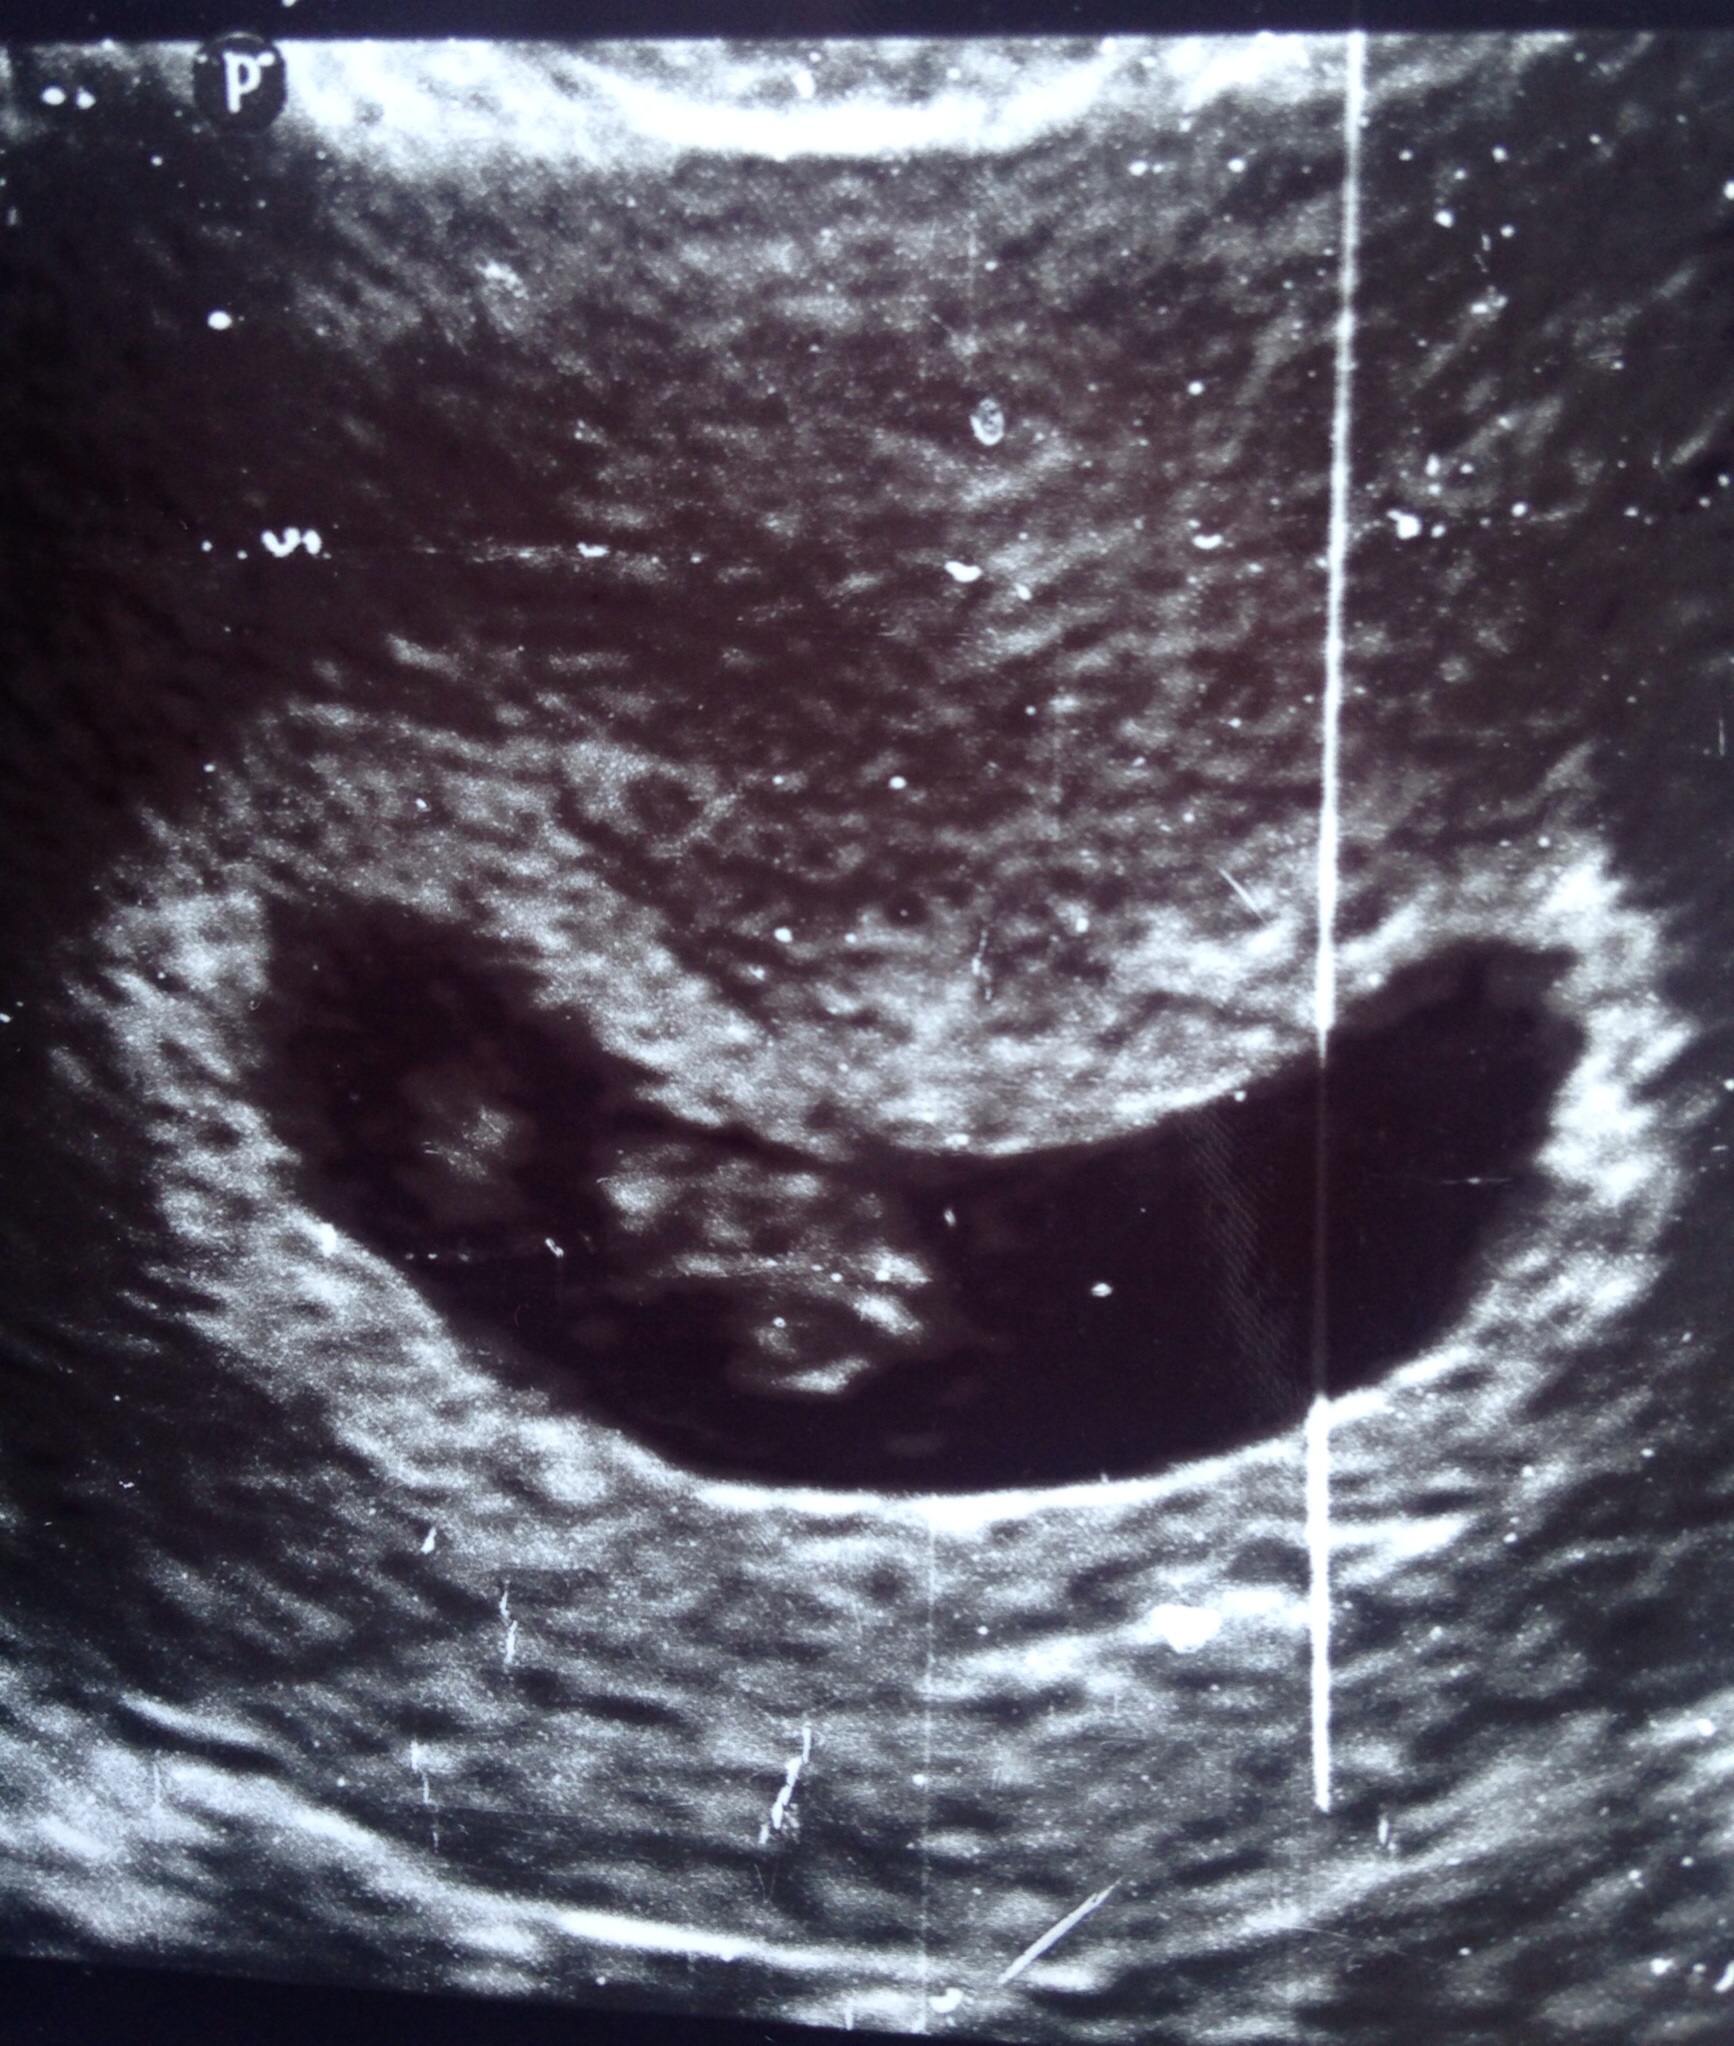

Had my first ultrasound yesterday and was so happy to hear good news. After a previous loss I had been a nervous wreck with this pregnancy, but now my nerves have calmed quite a bit. Me and my husband both went to the appointment and it was so cute to see him choke up at the sound of baby's heart beat as well as seeing our little bean. I of course was just as emotional because quite frankly it is the cutest lil blob I've ever seen! Baby is measuring right on time and has a healthy heartbeat of 164. Although I know the "safe zone" hasn't been passed it's great to see baby is doing great so far. I have the highest hopes! After seeing so many first ultrasound threads I thought I'd share!